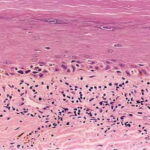

onset of a nodule, with development of ulceration . However, some acral melanomas may be deeply invasive while remaining quite flat because the thick stratum corneum seems to act as a barrier to exophytic growth. Histopathology. The lesions are termed lentiginous because the majority of the lesional cells are single and located near the dermal-epidermal junction, especially at the periphery of the lesion . However, usually some tumor cells can be found in the upper layers of the epidermis, especially near areas of invasion in the center of the lesions. The histologic picture differs from that of lentigo maligna because of irregular acanthosis, the lack of elastosis in the dermis, and the frequently dendritic character of the lesional cells . Early in situ or microinvasive lesions may show, especially at the periphery, a deceptively subtle histologic picture consisting of an increase in basal melanocytes and hyperpigmentation with only focal atypia of the melanocytes. However, in the center of the lesions, there is usually readily evident uniform, severe cytologic atypia. There may be a lichenoid lymphocytic infiltrate that may largely obscure the dermal-epidermal junction, and in some cases this may be so dense as to simulate an inflammatory process. In most of the lesions, both spindle shaped and rounded, pagetoid tumor cells are seen, and, in many cases, pigmented dendritic cells are prominent. Pigmentation is often pronounced, resulting in the presence of melanophages in the upper dermis and of large aggregates of melanin in the broad stratum comeum. As in lentigo maligna, when tumorigenic vertical growth phase is present, it is often of the spindle cell type and not uncommonly desmoplastic and/or neurotropic. In |